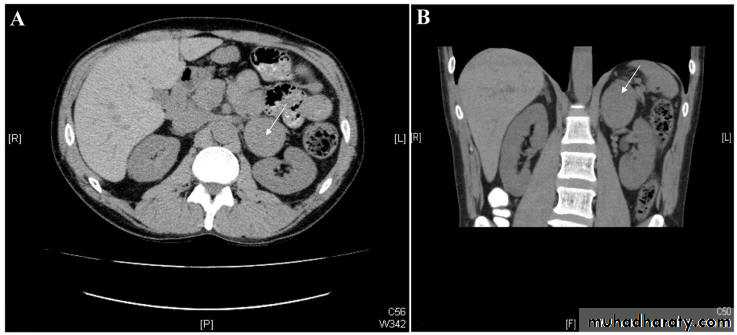

Retroperit abscess

Peritoneal cavity and retroperitoneal